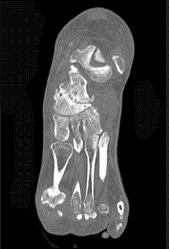

问题 男,68岁,脚行走时疼痛,无红、肿、热、痛,结合图像,最可能的诊断是 ( )

选项 A、骨嗜酸性肉芽肿 B、骨肉瘤 C、骨结核 D、骨转移瘤 E、骨性关节炎

答案 E